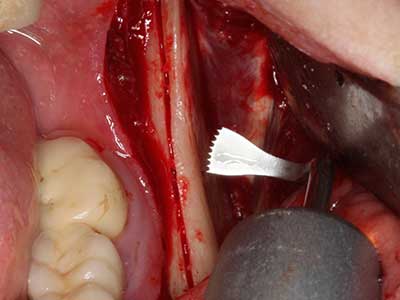

Si es preciso realizar intervenciones quirúrgicas en las que el hueso está en contacto directo con estructuras sensibles, como son los vasos sanguíneos o los nervios, los instrumentos rotativos presentan un enorme potencial de provocar lesiones iatrogénicas. Así, precisamente en la representación de nervios después de una lesión iatrogénica, o en el transcurso de la lateralización de un nervio para resecciones, reconstrucciones o incorporación de implantes, los equipos piezoeléctricos pueden resultar muy útiles para preparar la tapa ósea y retirar las partes de tejido duro cercanas al nervio (fig. 17-20). Por lo general, un ligero contacto del cordón nervioso con el inserto piezoeléctrico no tiene consecuencia alguna; ahora bien, un procedimiento poco cuidadoso con movimientos tipo sierra o piezas de trabajo sobre la base ósea aún existente puede provocar lesiones nerviosas temporales o incluso permanentes. Con todo, el riesgo de sufrir una lesión de este tipo se considera significativamente inferior que en los casos en los que se utilizan sierras y fresas (Pereira, Gealh et al. 2014).

En la extracción de bloques óseos la piezocirugía también presenta ventajas adicionales: Además de la alta precisión en la osteotomía que ya se ha descrito antes, se ha comprobado que el uso de los delgados insertos de sierra resulta especialmente cuidadosas con el hueso. Frente a esto, sobre todo cuando se usan las fresas de Lindemann, cabe esperar pérdidas en la extracción significativamente más altas debido al mayor grosor de la parte frontal del cabezal (Lakshmiganthan, Gokulanathan et al. 2012). La separación basal que se necesita en particular en los injertos de bloque extraídos de forma retromolar se ve facilitada mediante sierras perpendiculares especialmente previstas a tal fin, lo que permite considerar que la cirugía piezoeléctrica es un procedimiento preciso y seguro para la obtención de bloques de hueso en el área retromolar (Happe 2007) (fig. 1-12).